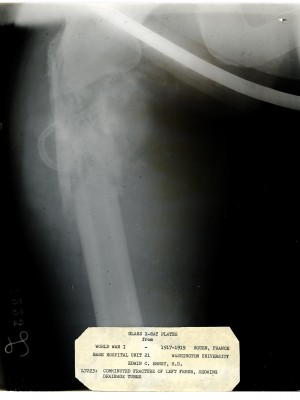

Dr. Edwin Ernst, an only child born to St. Louis residents Charles and Catherine Ernst, was a notable Roentgenologist, a physician who specializes in radiological work. Dr. Ernst studied at Washington University in St. Louis and later at Moravian College in Bethlehem, Pennsylvania earning his advanced degrees. For two years he served as a resident physician at the St. Louis Mullanphy Hospital before leaving to pursue a private practice. When the United States formally entered the war in 1917, Ernst left St. Louis to become chief radiologist at Base Hospital 21. He was discharged honorably in 1919 with the citation of Major. His collection consist of x-ray images taken at Base Hospital 21 as well as drawings of radiological equipment and photographs.